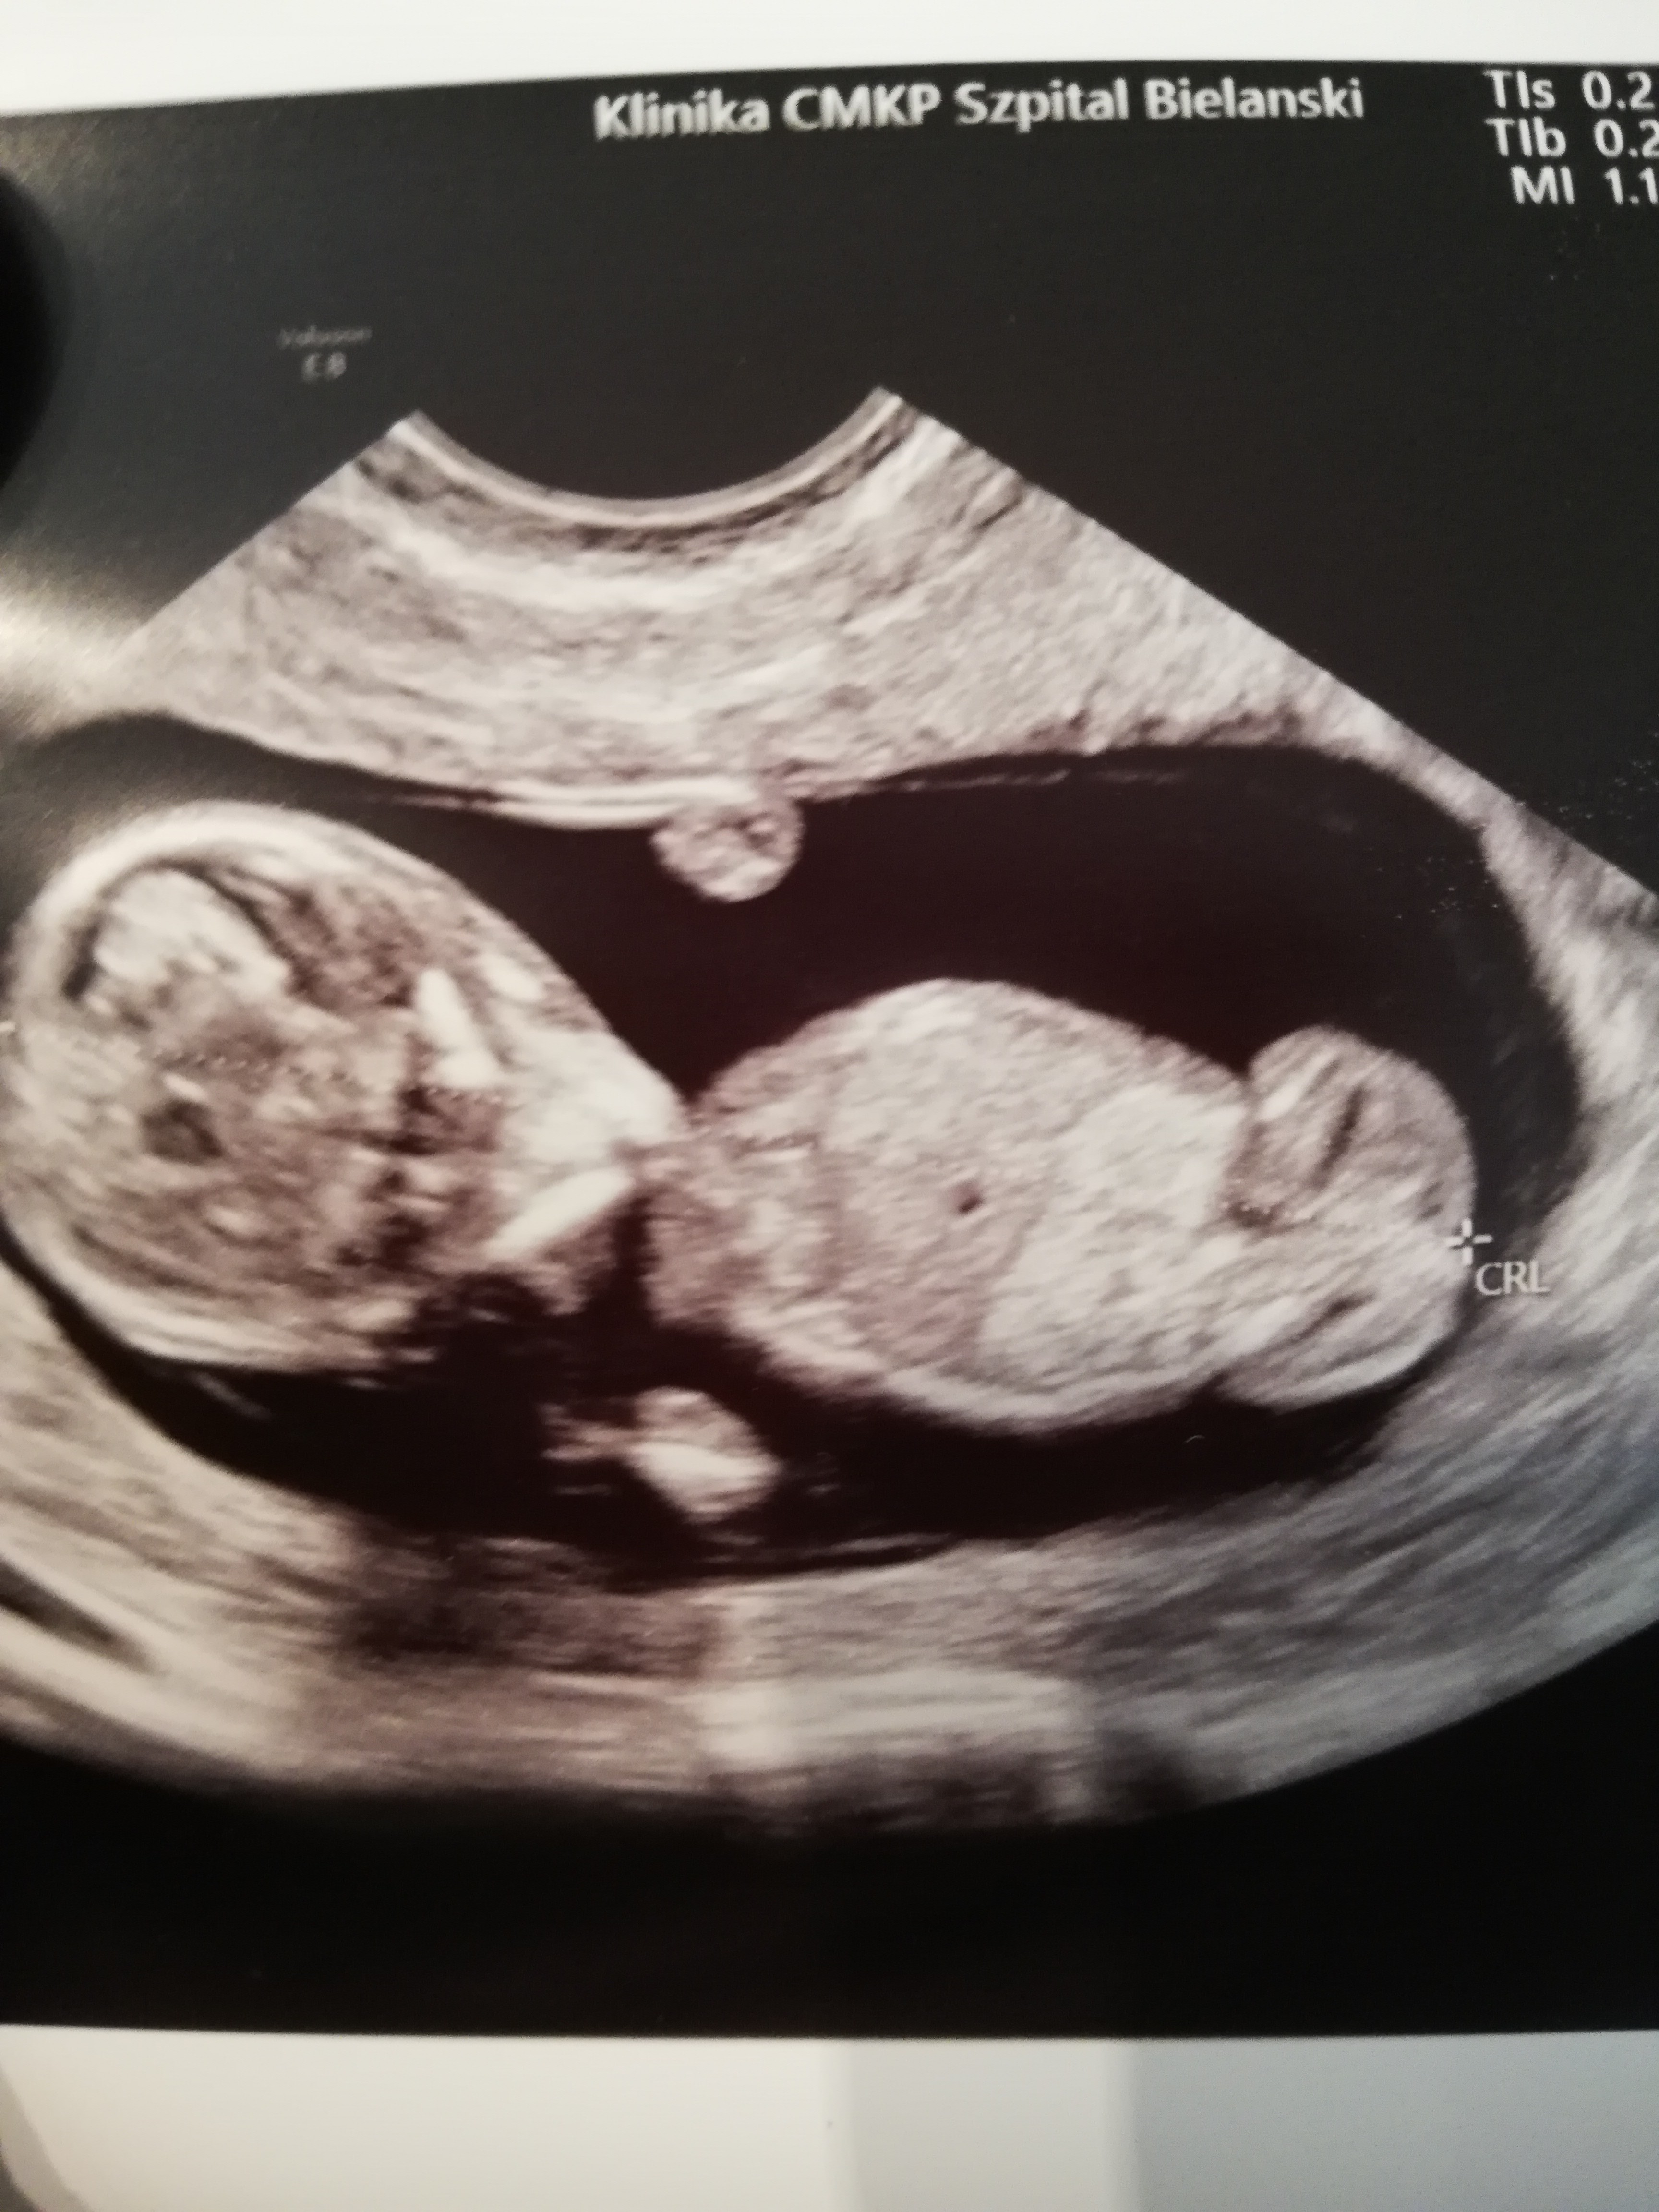

Melduję się po prenatalnym USG. Wszystko jest dobrze. Mam tylko do dziewczyn pytanie ile mialyscie DV PI (przepływy)? To miało byś istotne u mnie ale nie mogłam się już dopchac do mojego lekarza i nie wiem jakie są normy na necie też nic nie pisze

12 i 2 dni